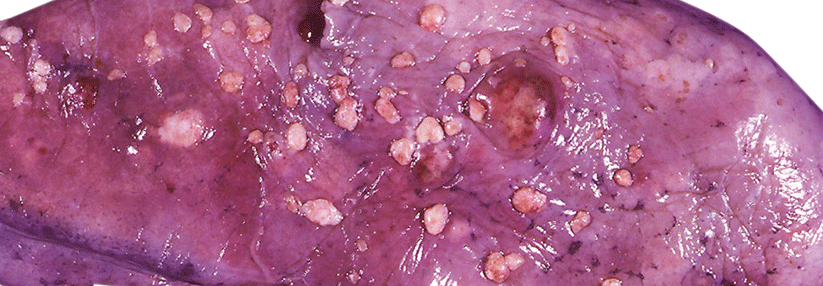

Ob Lynch-Syndrom oder nicht – Keimbahnmutationen zu identifizieren ist ein wichtiger Bestandteil für die Behandlung von Tumoren des Endometriums. Der Nutzen von Multigen-Panels wurde dafür in einer prospektiven Studie getestet.

So hat sich die Mismatch-Reparatur-Defizienz als Charakteristikum des Lynch-Syndroms beim Endometriumkarzinom als wichtiger Marker für eine Behandlung mit Checkpoint-Inhibitoren erwiesen. Die Testung mittels Multigen-Panels direkt bei Diagnose eines Endometriumkarzinoms bietet zudem die…